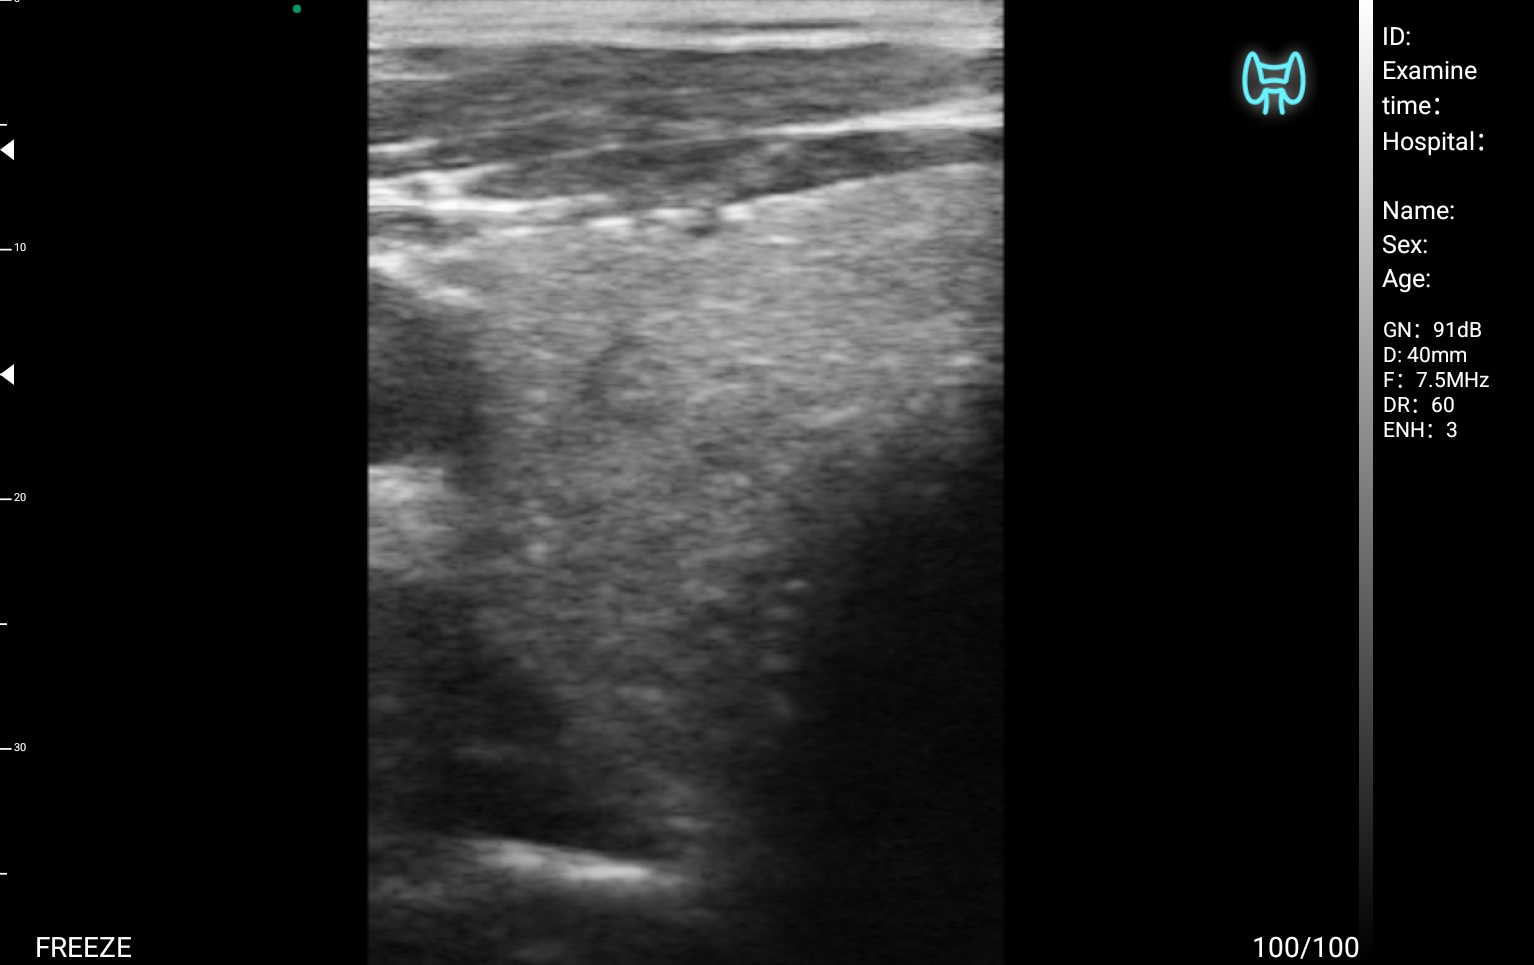

Η χρήση των ασύρματων κεφαλων MedBridge Echo Wave, ειδικά σχεδιασμένης για ενδοκρινολογικές ιατρικές πράξεις, ενισχύουν περαιτέρω την κλινική ακρίβεια και την αποτελεσματικότητα της διαχείρισης των ασθενών. Οι κεφαλές MedBridge Echo Wave επιτρέπουν την καθοδήγηση διαγνωστικών και θεραπευτικών παρεμβάσεων, όπως παρακεντήσεις και βιοψίες, τον ακριβή εντοπισμό και τη μορφολογική αξιολόγηση νεοπλασματικών αλλοιώσεων, καθώς και την παρακολούθηση της ανταπόκρισης στη θεραπεία. Παράλληλα, διευκολύνει τη διενέργεια ελάχιστα επεμβατικών πράξεων, προσφέροντας υψηλά επίπεδα ασφάλειας και ακρίβειας.

Ολες οι παραπάνω απεικονιστικές εξετάσεις έχουν ληφθεί από φορητή συσκευή όπως: Apple Iphone, Tablet, Samsung Mobile Phones και διάφορες άλλες φορητές συσκευές.